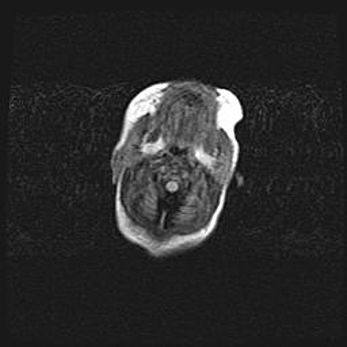

Лейкомаляция с кистозно-глиозной дегенерацией головного мозга.

Возраст: 2 месяца 25 дней

Вес: 6400 г

Окружность головы: 40 см

Срок гестации: 41 неделя

Лейкомаляцию относят к ишемически-гипоксическим повреждениям головного мозга, диагностируемым у новорожденных. При лейкомаляции в головном мозге обнаруживают очаги некроза, возникшие после тяжелой гипоксии и нарушения кровотока. В процессе морфогенеза очаги проходят три стадии: 1) развития некроза, 2) резорбции и 3) формирования глиозного рубца или кисты. Перивентрикулярная лейкомаляция (ПЛ) встречается примерно в 12% случаев среди новорожденных, обычно – у недоношенных детей, причем, частота ее зависит от массы, с которой младенец появился на свет. Наибольшее число малышей страдает лейкомаляцией, если масса при рождении 1500-2500 г.